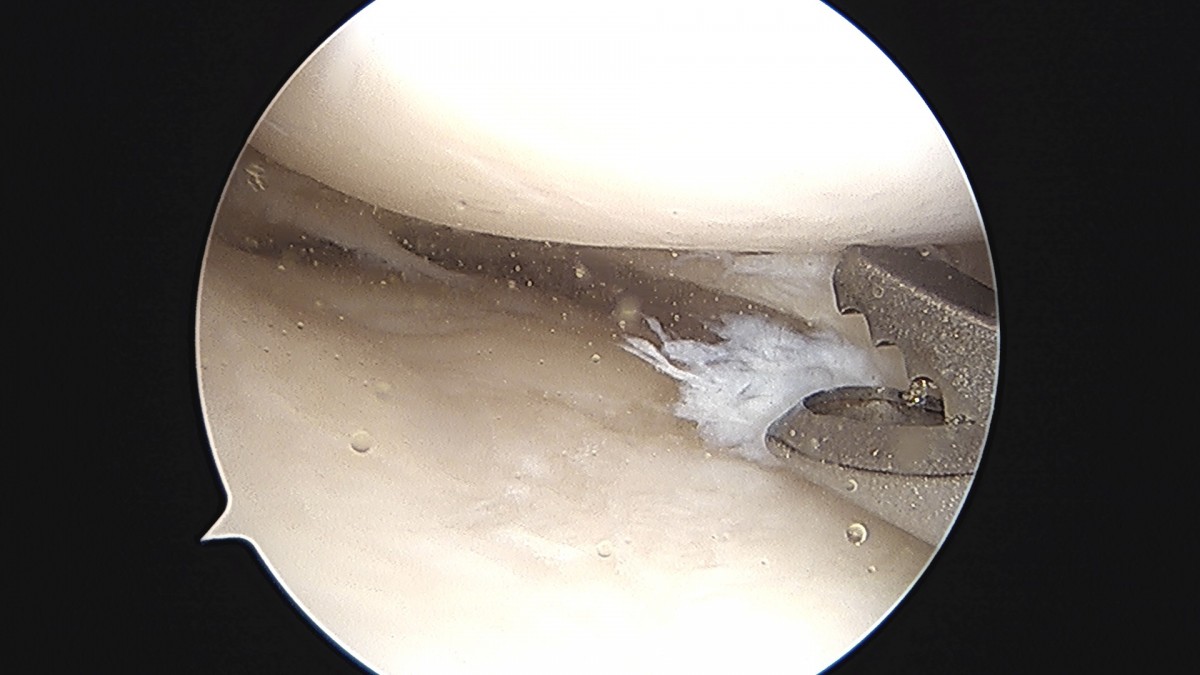

이재상원장님 무릎 반월상 연골판 절제술 강일O 환자

dae765e4d9ac96aee867c9d6292d8784_1758006724_8897.jpg